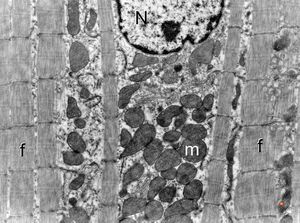

normal cardiomyocyte … longitudinal section(N - nucleus, m … mitochondria, f - myofilaments)